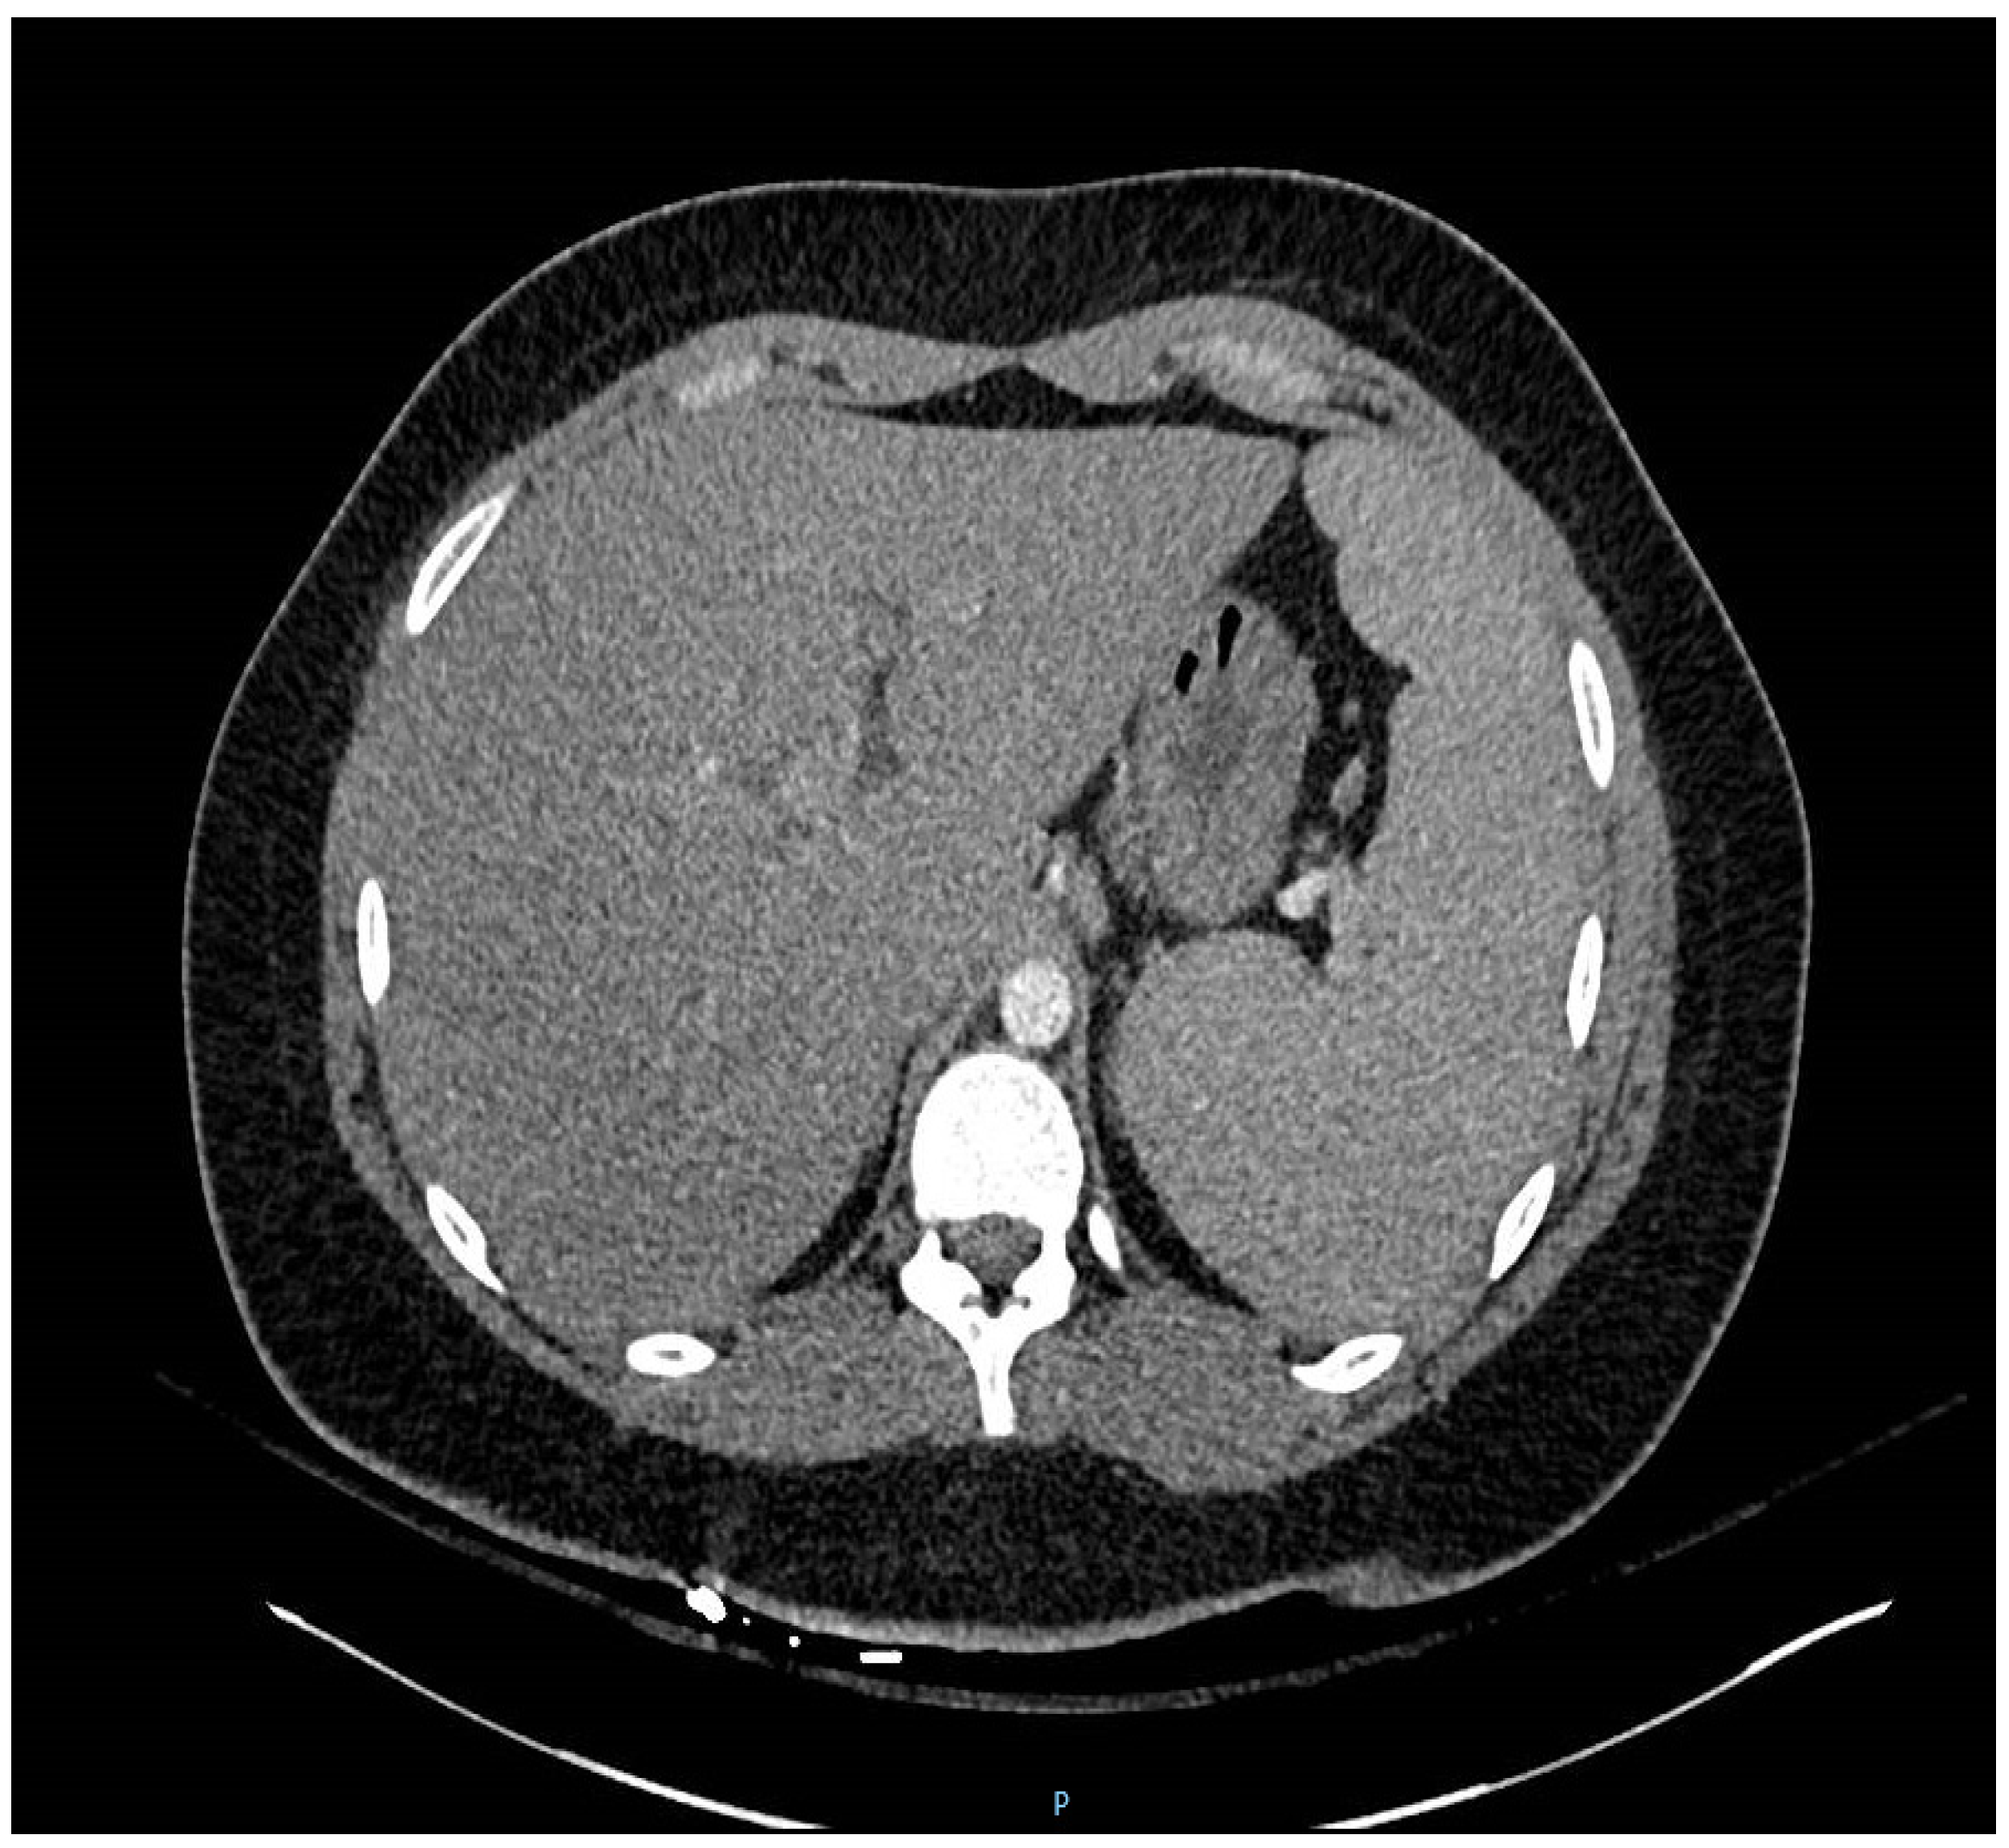

Unexplained Dyspnea in a Young Adult with Epstein–Barr Virus Infectious Mononucleosis: Pulmonary Involvement or Co-Infection with Mycoplasma pneumoniae Pneumonia?

2. Case